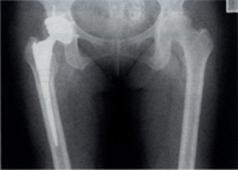

加齢や酷使あるいは外傷(微小外傷の蓄積のこともあります。)などによって発生する 一次性のものと、先天性股関節脱臼や臼蓋形成不全から続発する二次性のものとに分類されます(図1)。二次性のものの中には、大腿骨頭無腐性壊死(アルコール依存やステロイド連用によって若年でも発症します。)から移行することもあります。

(図1)

変形性股関節_01_1

正常股関節

変形性股関節_01_2

臼蓋形成不全症

変形性股関節

変形性股関節症